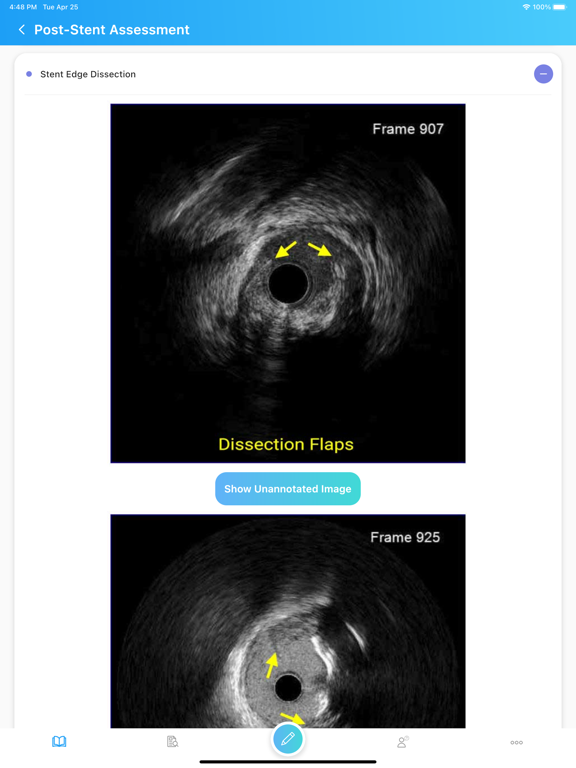

The IVUSAID App is a free educational mobile application which has been developed to teach medical professionals how to use intravascular ultrasound (IVUS) for PCI guidance based on the current guidelines using our extensive experience and large database of complex coronary cases. Despite the growing body of evidence for clinical benefits of IVUS-guided PCI, IVUS remains underutilized in much of the world including the United States. Challenges in image interpretation and education are among the barriers to widespread adoption of IVUS in everyday clinical practice. Mount Sinai Heart is a global leader within the field of interventional cardiology as well as mobile apps development. The myriad of cases and pathology which are seen in The Mount Sinai Cardiac Catheterization Laboratory make it the perfect center to educate medical professionals within this field. The Key Concepts section of IVUSAID describes principles of IVUS, image acquisition, and concepts of ultrasound behavior in various tissues. The Image Interpretation section of the app has dozens of representative cross-sectional images, videos, and descriptions of plaque types, stent apposition and expansion, artifacts, and more. A short video for each type of lesion or artifact and post-stent findings, in addition to an annotated representative cross section aims to overcome a major limitation of any article or book on IVUS which present a static image, since the actual IVUS pullback is dynamic. Twenty-one complex coronary cases demonstrate IVUS guidance in a variety of patient presentations and lesions including ACS, LM bifurcation, severely calcified lesions and calcified nodules, spontaneous coronary artery dissection, and malapposed stents as well as how IVUS was used to inform treatment decisions. An extensive quiz section helps deliver educational content in a more interactive format where answers are accompanied by detailed explanations and references. We hope that IVUSAID will help techs, fellows, and early-career physicians incorporate IVUS in their daily practice for stent sizing, post-stent optimization, and identification of appropriate treatment strategies.